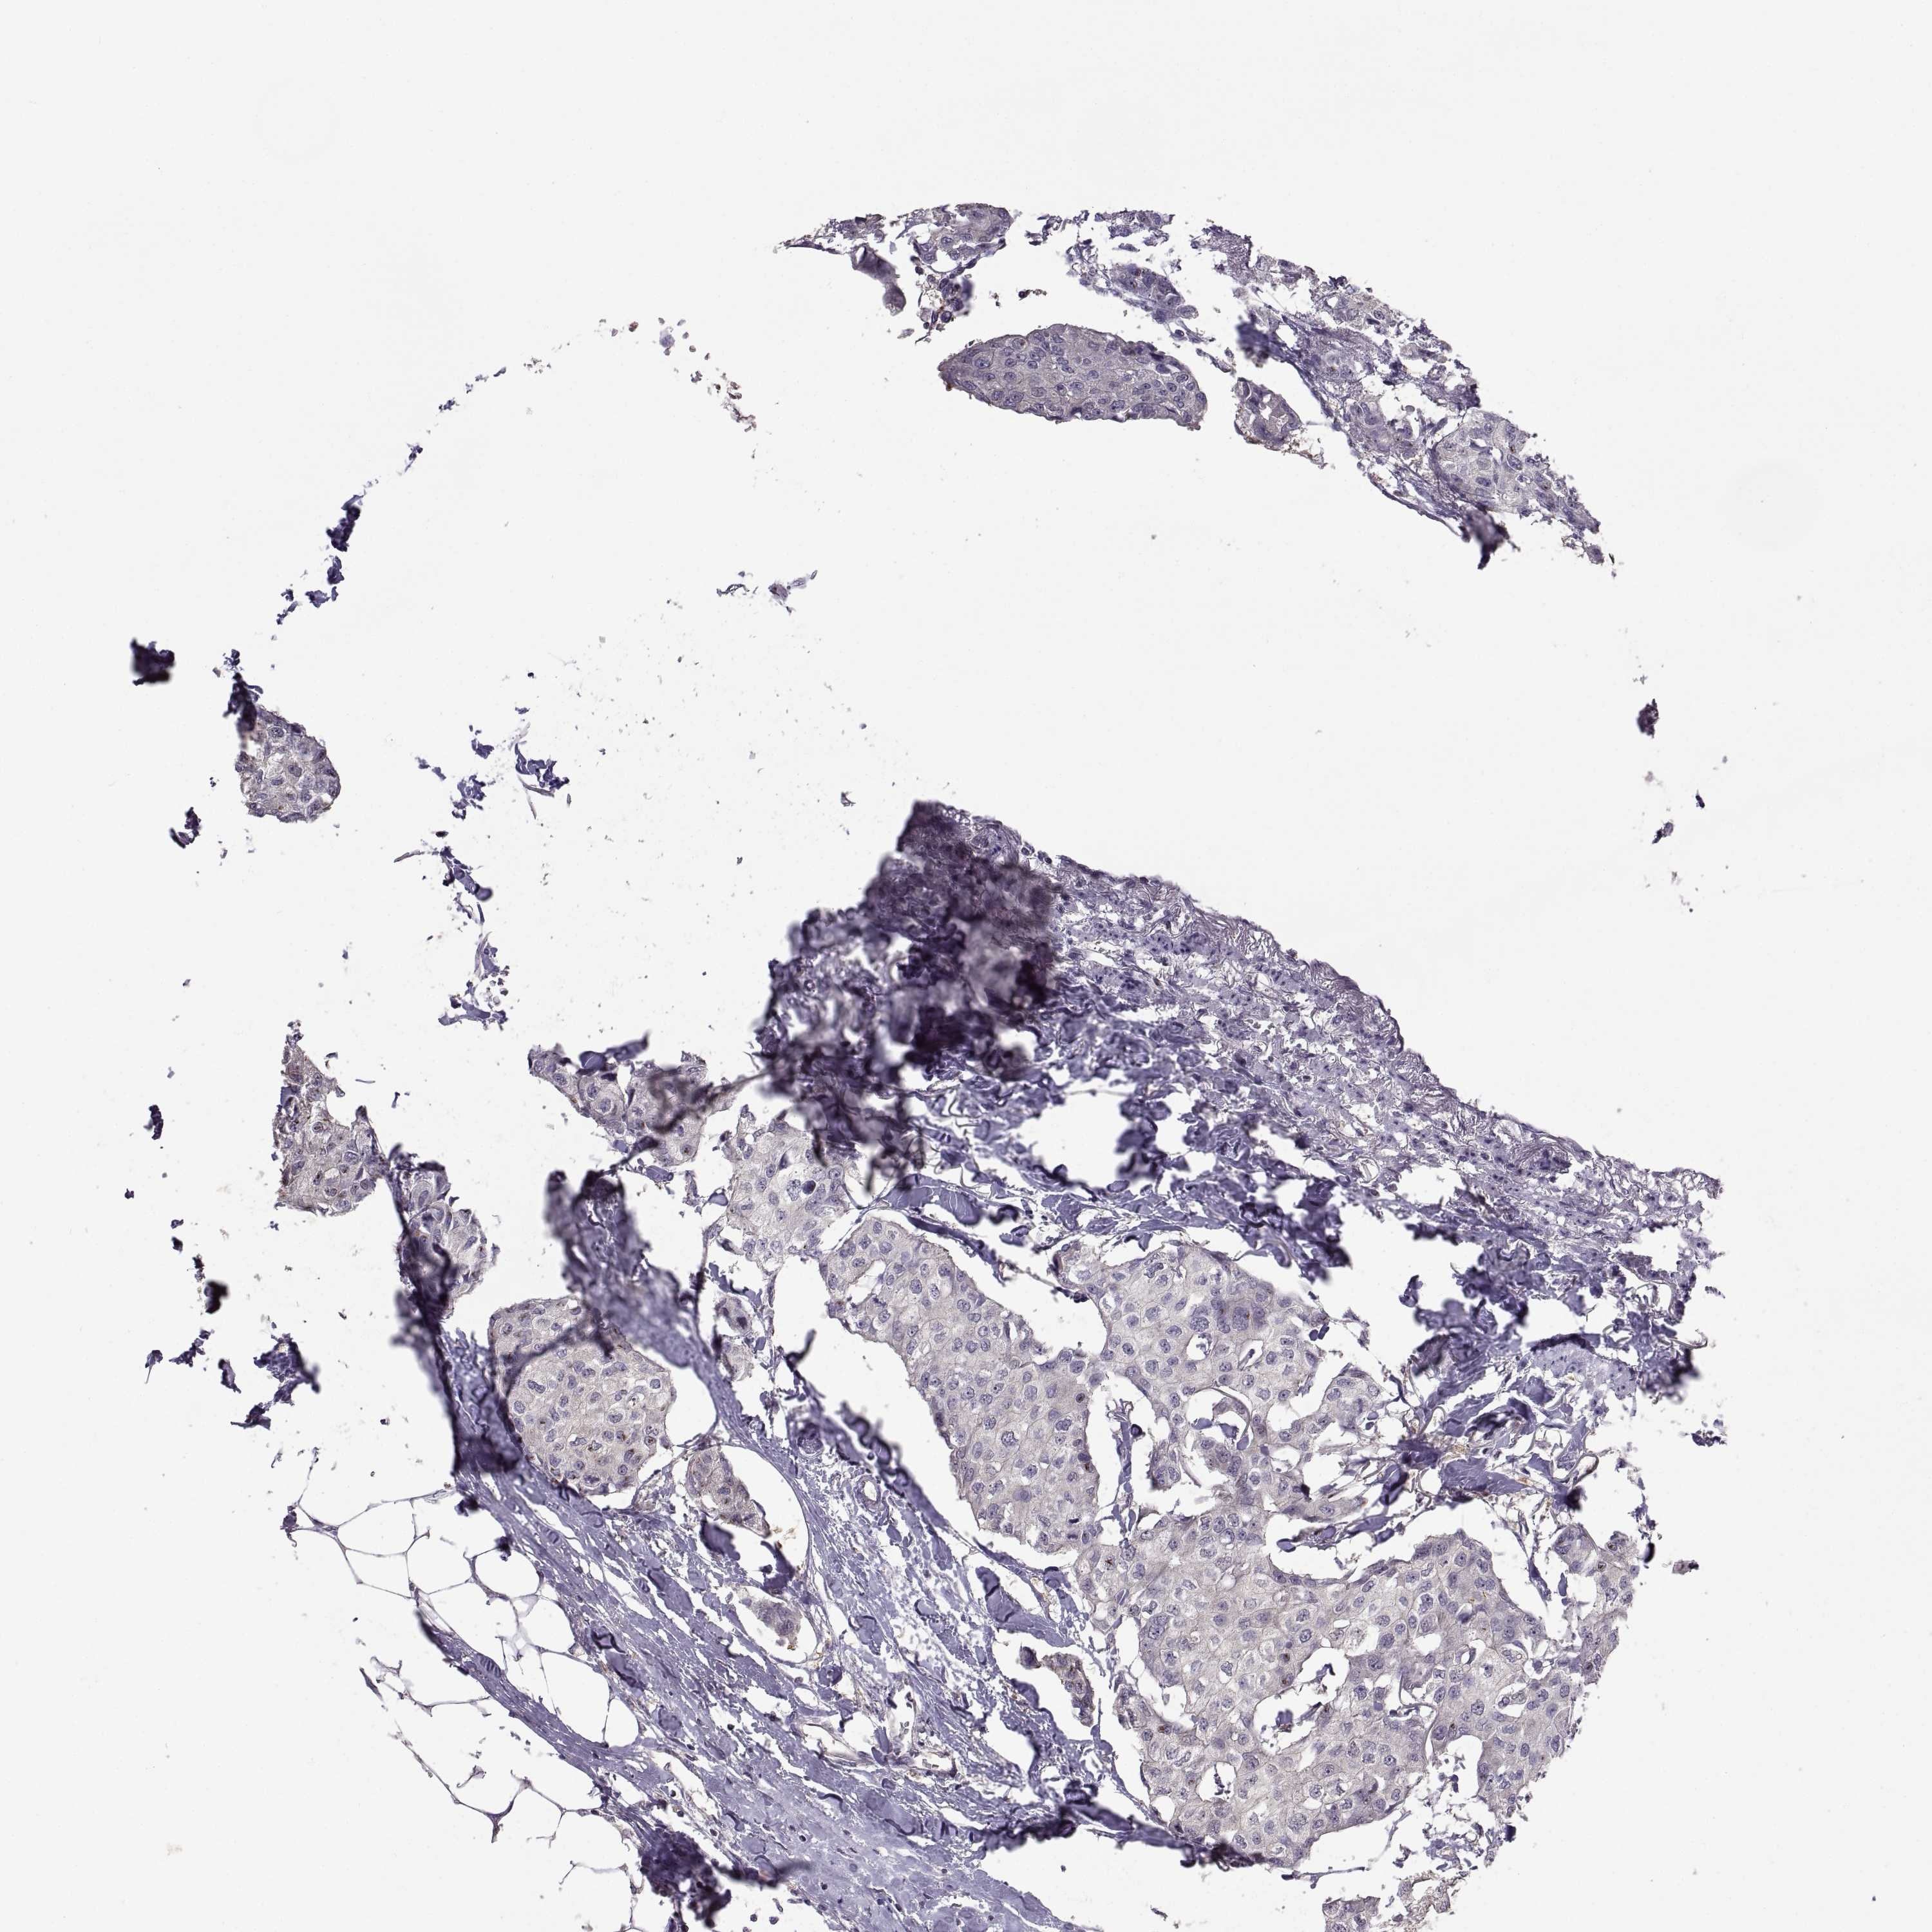

CANCER BREAST CANCER Show tissue menu

BRCA TCGA BRCA VALIDATION PROTEIN EXPRESSION

Breast cancer

Human cancer